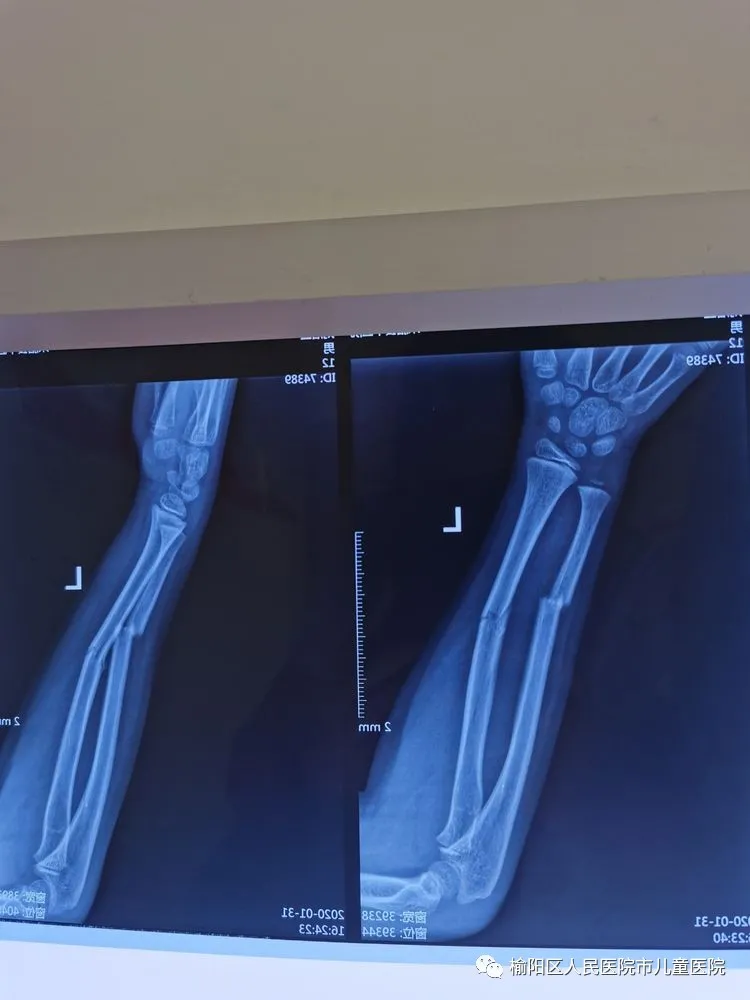

榆陽區(qū)人民醫(yī)院骨科——彈性髄內(nèi)針應(yīng)用分享

患兒12歲,因外傷致左尺橈骨骨折

復(fù)位外固定后家屬不滿意

在全麻下行彈性髄內(nèi)針微創(chuàng)閉合治療

術(shù)后5個(gè)月,完美愈合。

彈性髄內(nèi)針治療小兒四肢骨折優(yōu)點(diǎn):手術(shù)時(shí)間短,創(chuàng)傷小,住院時(shí)間短,骨折愈合快,費(fèi)用低。